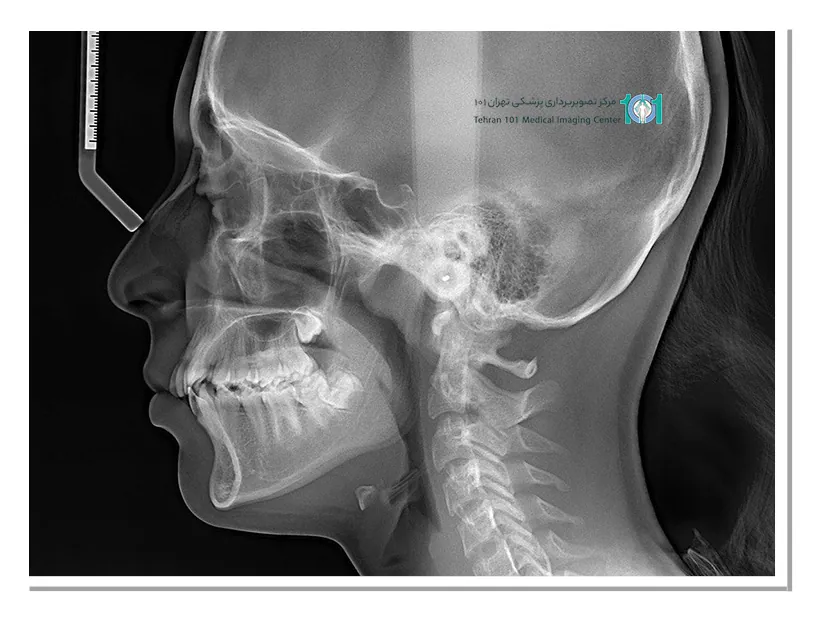

توموگرافی ساده و کامپیوتری (CT): توموگرافی ساده تصاویر دوبعدی را ارائه میدهد و به آن رادیوگرافی سنتی داخل دهانی یا پانورامیک نیز گفته میشود.

توموگرافی کامپیوتری (CT) تصاویر سهبعدی ارائه میدهد و برای تشخیص و درمان بیماریهایی مانند اختلالات مفصل گیجگاهی فکی (TMJ)، نهفتگی دندان و تعیین محل کاشت ایمپلنت استفاده میشود.

ارتودنسی: درصورتیکه برای ارتودنسی و درمان ناهنجاریهای فک و صورت نیاز به ارزیابی توسط متخصص رادیولوژی فک و صورت وجود دارد، دندانپزشک ممکن است شما را به او ارجاع دهد.